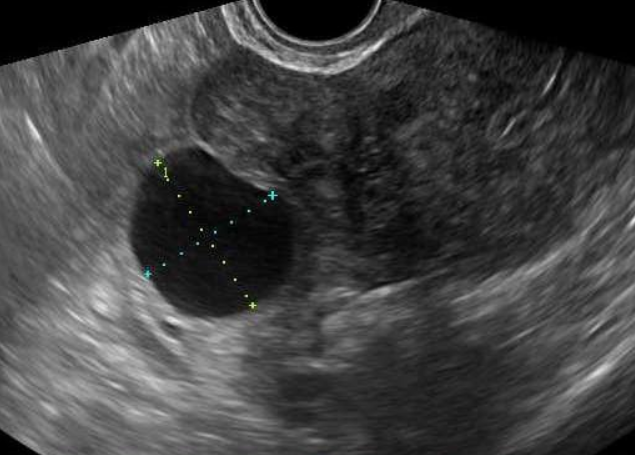

자궁·난소 등의 이상 소견을 확인하는 여성생식기 초음파 검사는 여성에서 흔히 발생하는 질환인 자궁근종, 난소 낭종 등을 진단하기 위한 기본적인 검사방법임에도 불구하고 그간 4대 중증질환(암·심장·뇌혈관·희귀난치)에 한해 제한적으로 건강보험이 적용됐었다.

보건복지부는 4대 중증질환 환자뿐만 아니라 자궁·난소 등 여성생식기 부위에 질환이 있거나 질환이 의심돼 의사가 초음파 검사를 통한 진단이 필요하다고 판단한 경우 건강보험이 적용된다고 밝혔다.

여성생식기 초음파 검사의 보험적용 범위는 의사의 판단 하에 자궁, 난소, 난관 등에 질환이 있거나 질환을 의심하는 증상이 발생하여 의학적으로 검사가 필요한 경우까지로 확대된다.